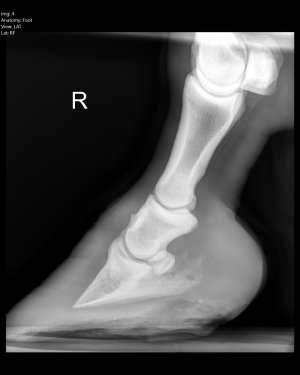

Good that you found out now before you got a huge laminitis episode. This is completely and utterly fixable though, and relatively quickly. Once the inflammation comes down, the rotation will reduce and all will be good. It’s just management changes now - trial and error (we got past the more general vet to the practice specialist eventually and following her advice was the key!). Our Shetland was so so poorly with EMS induced laminitis and yet now you would never know. She’s skinnier than she’s ever been, but so long as we keep her on her strict diet and provide enough exercise, she’s sound as anything, in full work and very happy.

Personally I’d (at least short term) get shoes on him to help address quite clear balance issues. For a variety of reasons, more immediate comfort to assist with better movement (weight loss benefits). Reduce the risk of poor compensatory patterns (potential for soft tissue/arthritic changes).

One alignment is better and you have any weight/metabolic issues under control, by all means aim to remove the shoes.

I’m inclined to agree with ihw re putting shoes on in the short term to correct the imbalances, plus repeat x rays to monitor progress. That is what I did with my homebred with poor front foot balance. The shoes came off again later.